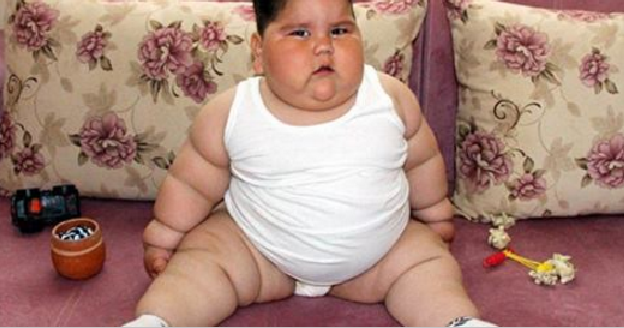

Vetëm 1 vjeç e gjysmë dhe peshon 32 kilogramë (Video)

Pesha anormale e fëmijës, i lindur nga 26-vjeҫarja Sevda Bekte dhe 32-vjeҫari Sedat, ka rënë në sy të të gjithë dhe është një problem shëndetësor që mjekët e kanë konsideruar si të pazakontë e madje as mjekët ende nuk kanë gjetur sëmundjen e saktë të tij.

Prindërit, të cilët jetojnë në Samsun, janë shokuar në fillim kur kanë panë djalin që rritej në mënyrë të pakontrolluar gjatë gjithë kohës.